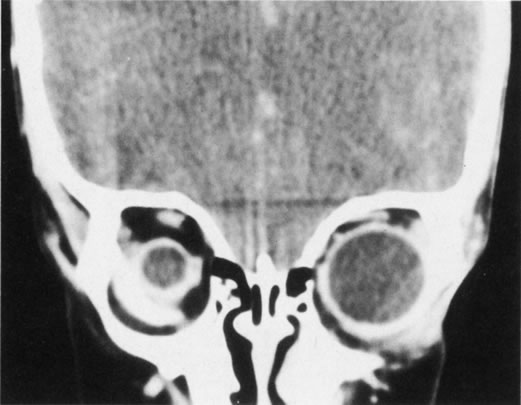

Fibrous dysplasia is a benign disorder characterized by an arrest of bone maturation that results in immature bone and osteoid in a cellular fibrous matrix. This congenital disease usually becomes clinically apparent in children and young adults. Fibrous dysplasia can extensively involve the facial bones and skull.24 The maxillary, frontal, and sphenoid bones are most commonly involved. Maxillary bone involvement can cause nasolacrimal duct obstruction. Involvement of the frontal and sphenoid bones may result in orbital asymmetry from contour deformities, vertical dystopia, and exophthalmos (Fig. 17). Radiographically, fibrous dysplasia appears as an expansile bone lesion with a characteristic ground-glass appearance (Fig. 18). Additional ocular complications include compressive optic neuropathy, oculomotor nerve palsy, and trigeminal neuralgia.25 Involvement of the sphenoid bone may result in narrowing of the optic canal, with secondary compressive optic neuropathy. Definitive treatment entails unroofing the optic canal by way of a transcranial approach, although high-dose steroids can be used as a temporizing measure.

Fig. 17. Fibrous dysplasia of the left maxilla has resulted in marked hypertrophy of the maxilla and cheek, lower eyelid ectropion, and hyperglobus of the left globe.